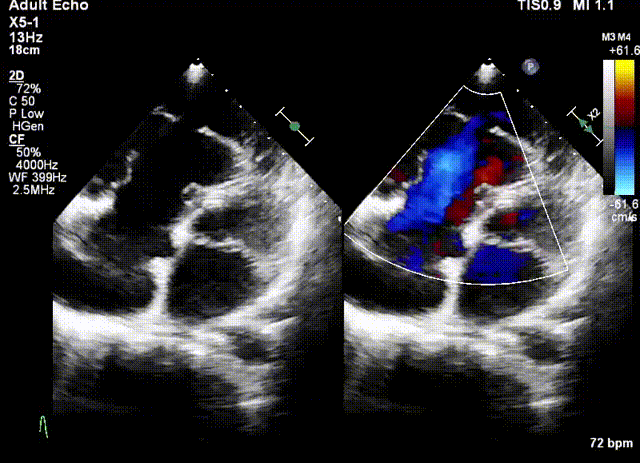

術(shù)前超聲

該例患者為79歲女性,NYHAⅢ級,心衰癥狀顯著,藥物(大劑量利尿劑)治療9個月后仍出現(xiàn)頑固性踝關(guān)節(jié)水腫。術(shù)前超聲心動圖提示三尖瓣重度反流(5+),右房右室擴大,三尖瓣瓣環(huán)擴張合并嚴重三尖瓣葉栓系,TAPSE 1.9cm,gap 23.2mm,PASP 30~35mmHg,LVEF 58%。